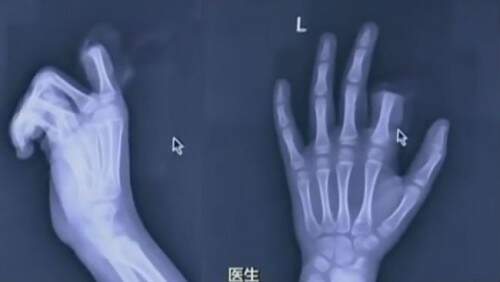

Médicos que fizeram a cirurgia de recolocação do membro não garantiram se a operação foi um sucesso. (Crédito: Reprodução)

No meio da discussão com o pai, o menino pegou uma faca e simplesmente decepou o próprio dedo. Os pais correram e levaram Xiaopeng e o pedaço do dedo cortado ao hospital. Já internado no Ruihua Affiliated Hospital of Soochow University, os médicos avaliaram que era possível recolocar o membro do menino através de uma cirurgia de emergência.

A operação levou três horas, mas os médicos não informaram se o procedimento foi um sucesso. “As crianças pequenas têm vasos sanguíneos muito finos, o que tornou a operação muito mais difícil”, afirmou Ren Zhourong, o médico responsável pela operação. “Se a operação for um sucesso total, o impacto deste incidente na mão esquerda de Xiaopeng deve ser mínimo.”